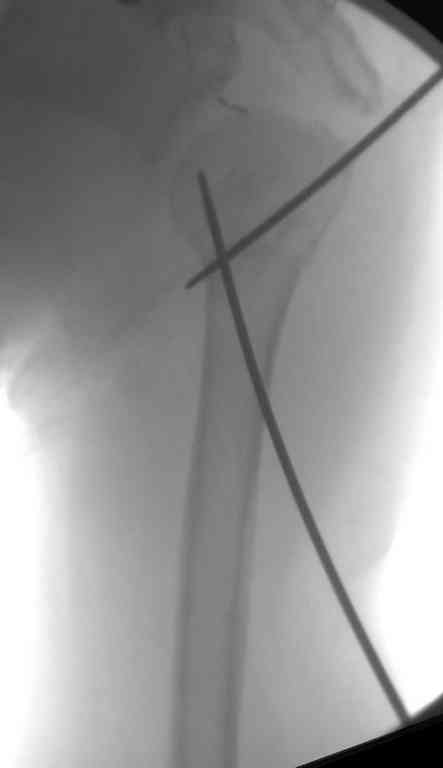

Сделали напряженными спицами по методике А.Ф.Лазарева со товарищи Репозиция сделана спицевым дистрактором, проксимальная спица была проведена в полскости деформации перпендикулярно оси наклонившейся головки. Получилось все довольно легко. Спицы малость покороче можно было сделать, ну да удалять потом легче будет.

Картинка в приложении.

Очень даже неплохо получилось. Молодцы! Лучше чем на 3D "репозиции".

В приложении. Схема простая - по спице в каждый отломок, полукольцо проксимально, кольцо дистально, два телескопа. Как уже писал, ключевым моментом было введение спицы в плоскости диформации проксимального

оттдела плеча.